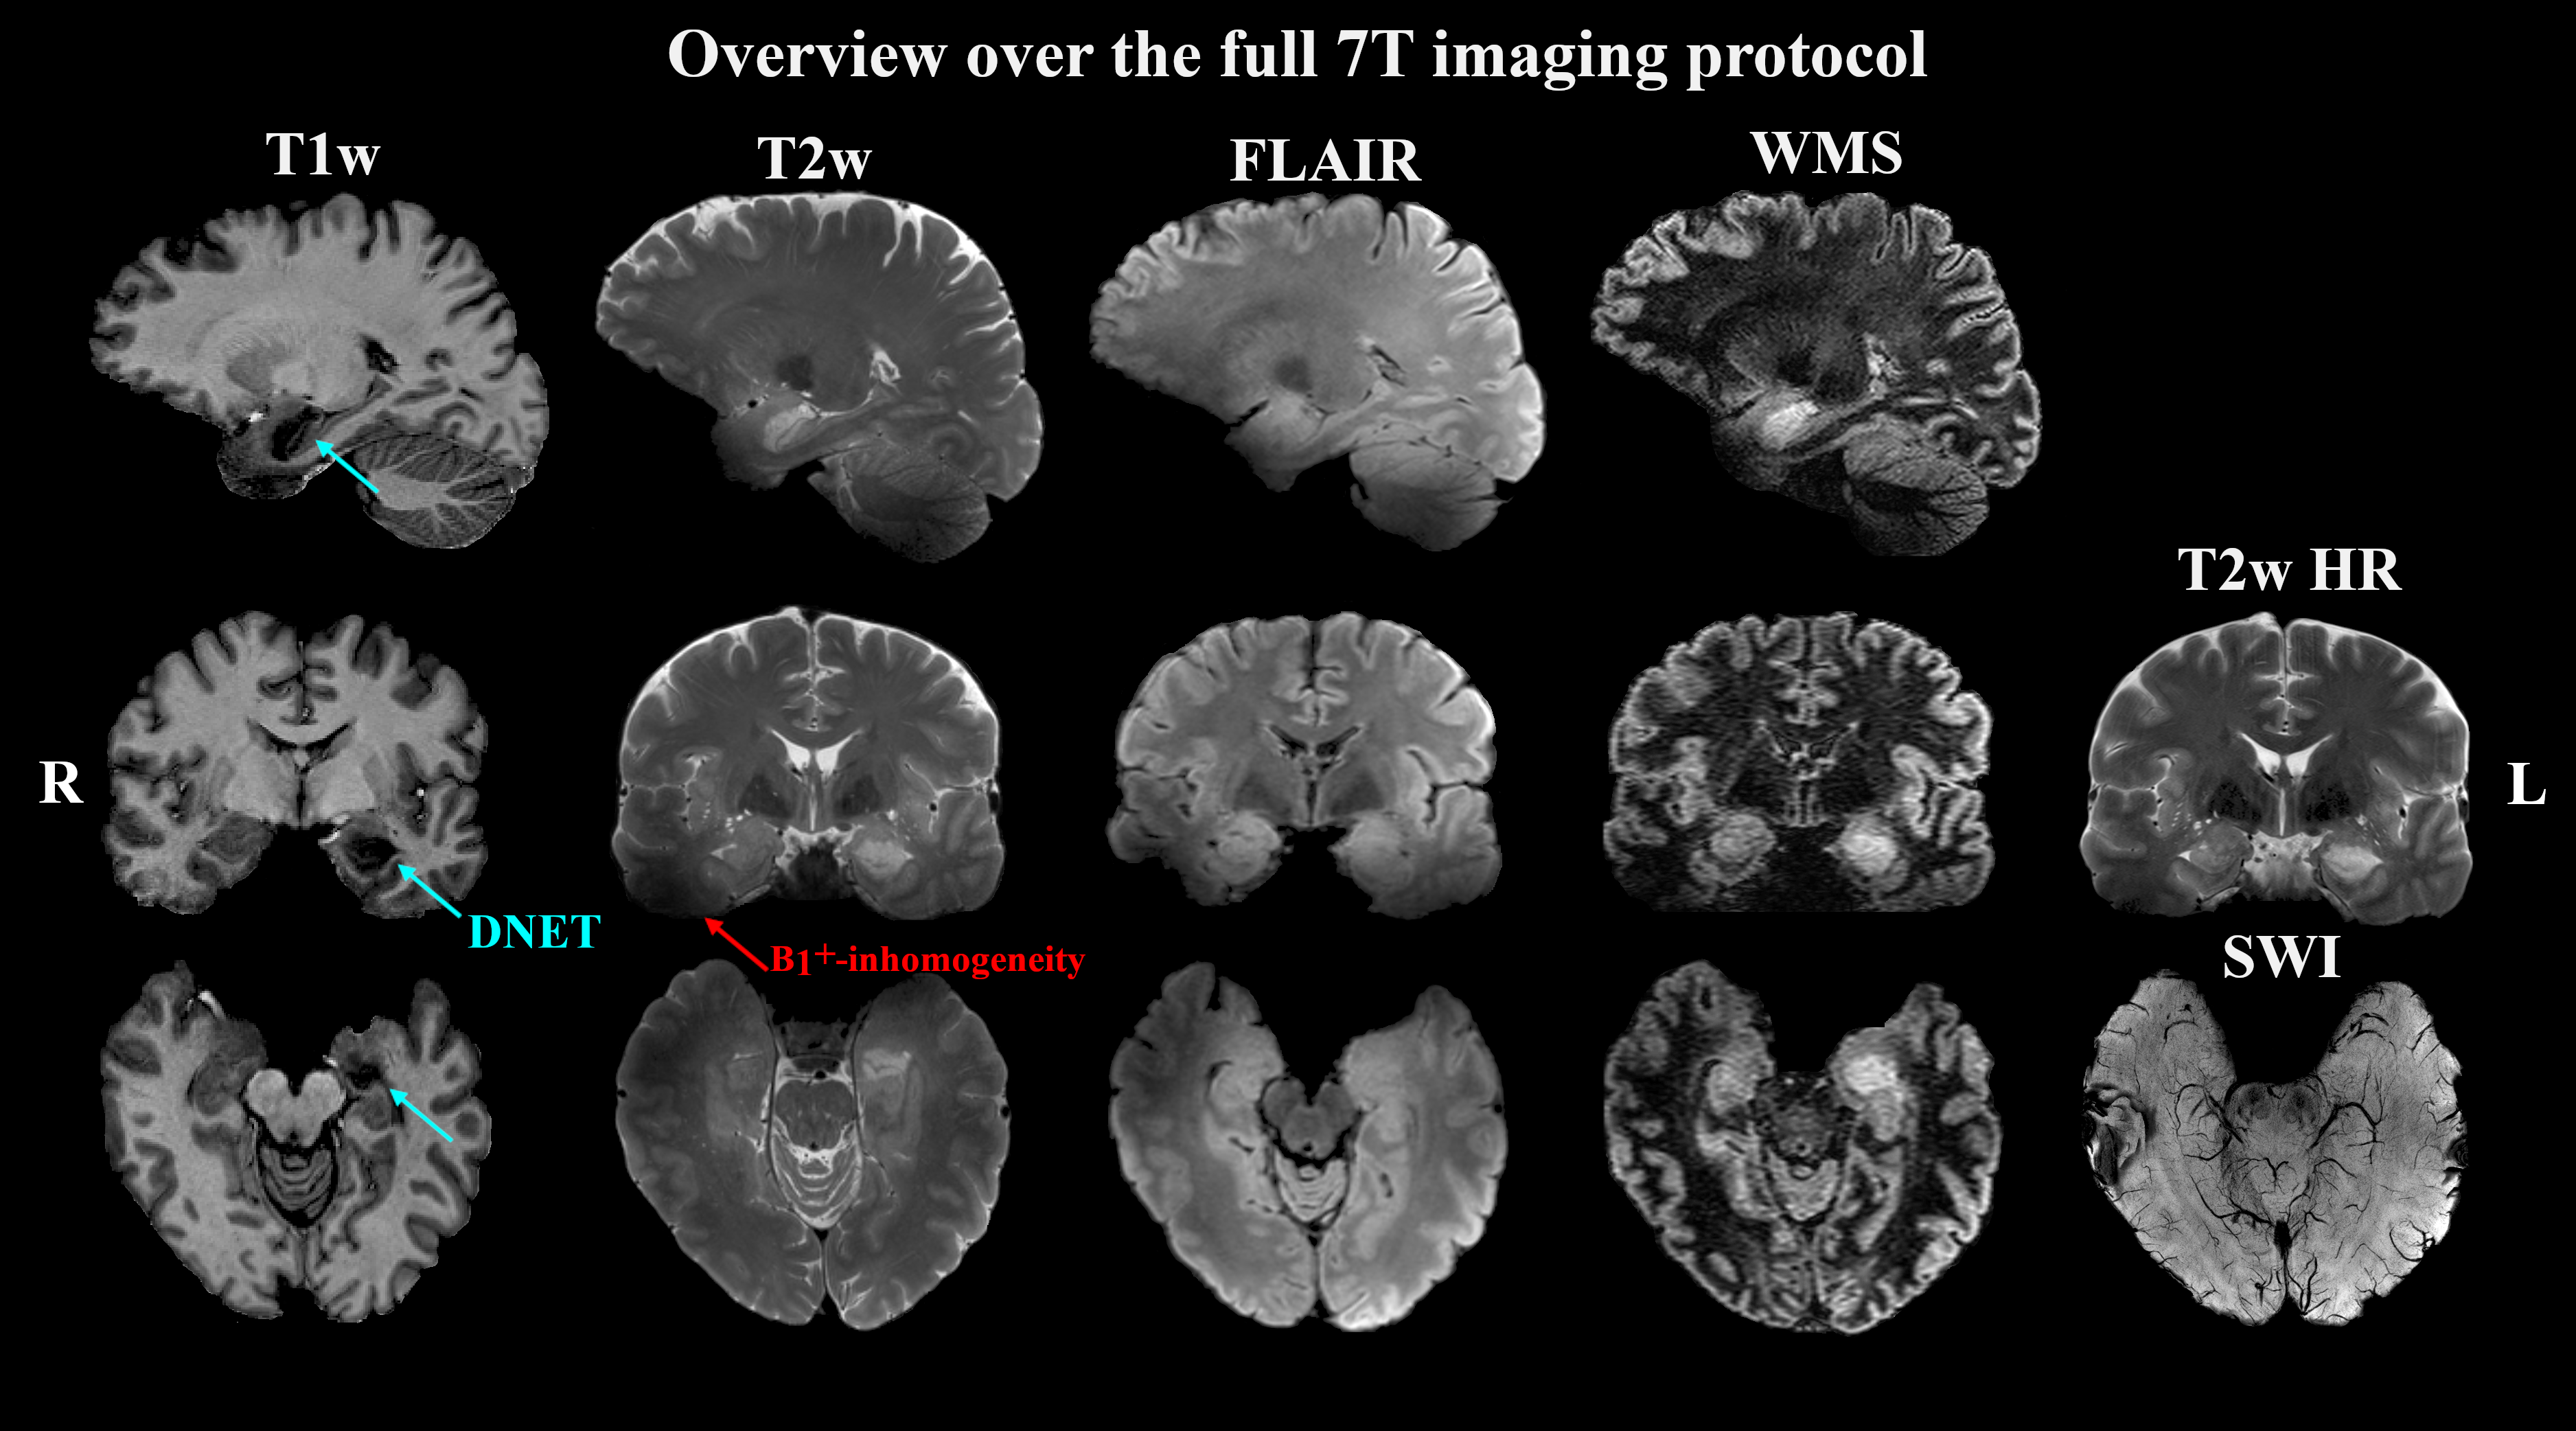

Of 41 recruited patients, 38 (age range 14-49 years, twenty female) completed the 7T protocol. The cohort included twenty-one 3T MRN cases and seventeen cases with insufficient clinical delineation. An example of 7T protocol quality is given in Figure 1. For 3T MRI, rater 1 reported a detection rate of 45% with a κ of 66% compared to 55% with a κ of 79% at 7. For the 22 patients with either 3T or 7T findings, mean confidence scores were 1.64±0.84 for 3T and 1.95±1.19 for 7T MRI (p=0.04).

Figure 1: The 7T epilepsy consensus protocol MRI contrasts in patient #22 with a histologically confirmed dysembryoplastic neuroepithelial tumour.